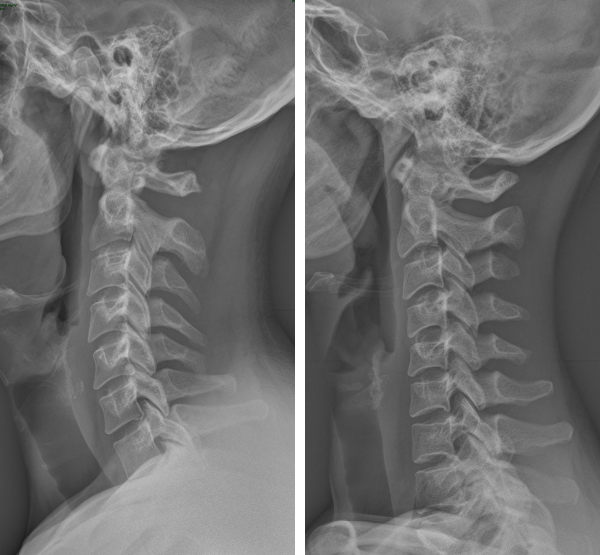

Zdjęcia rentgenowskie: z lewej strony – lordoza prawidłowa, z prawej – lordoza zniesiona.

Kręgosłup dzielimy na odcinki: szyjny, piersiowy, lędźwiowy, krzyżowy. Patrząc na kręgosłup z boku, zobaczymy, że nie jest on prosty. Wygięcia zwiększają jego odporność na działające na niego siły. Wypukłe wygięcie w kierunku pleców nazywa się kifozą, a wklęsłe w kierunku pleców – lordozą. Naturalnym wygięciem odcinka szyjnego jest lordoza. Zniesienie lordozy szyjnej to zmniejszenie tego wygięcia aż do wypłaszczenia.